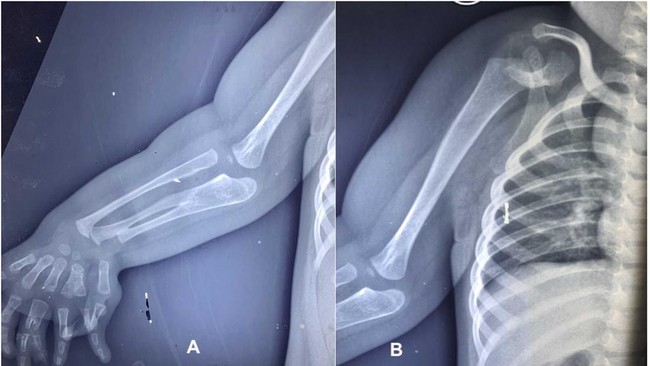

Seorang anak laki-laki berusia dua tahun di India, terlahir dengan kondisi langka anomali kongenital (congenital anomalies) yang membuat dirinya mengalami tiga lengan bawah dan duplikasi jari. Kasusnya ini diterbitkan dalam jurnal PlumX Metrics pada 2024, dengan judul ‘Congenital three-bone forearm – A rare disorder’.

Foto: jurnal PlumX Metrics

Jakarta - Anak berusia dua tahun lahir dengan kondisi langka. Saat lahir bayi tersebut memiliki banyak jari dan tulang lengan.